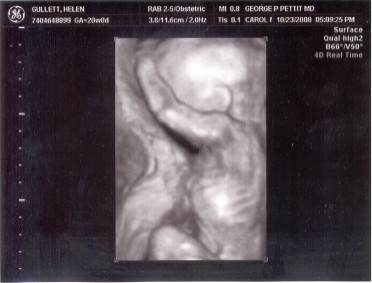

Ini adalah hasil foto yang diambil saat pemeriksaan dengan USG yang kedua kali. Saat itu, bayi saya berusia 20 minggu. Kami sudah berada di Amerika dan mesin yang digunakan adalah 3D/4D Ultrasonography dengan layar TV yang besar sekali dalam ruangan pemeriksaan. Juga, kami bisa mencetak foto-foto hasil USG langsung saat itu.

Dalam foto ini dapat dilihat dengan jelas kepala, telinga, tangan, kaki, tulang rusuk, dan bahkan sudah bisa dilihat apa jenis kelaminnya. Dia cukup malu saat kami ingin melihat wajahnya.

Berat badan saya saat itu sudah 54 kg!